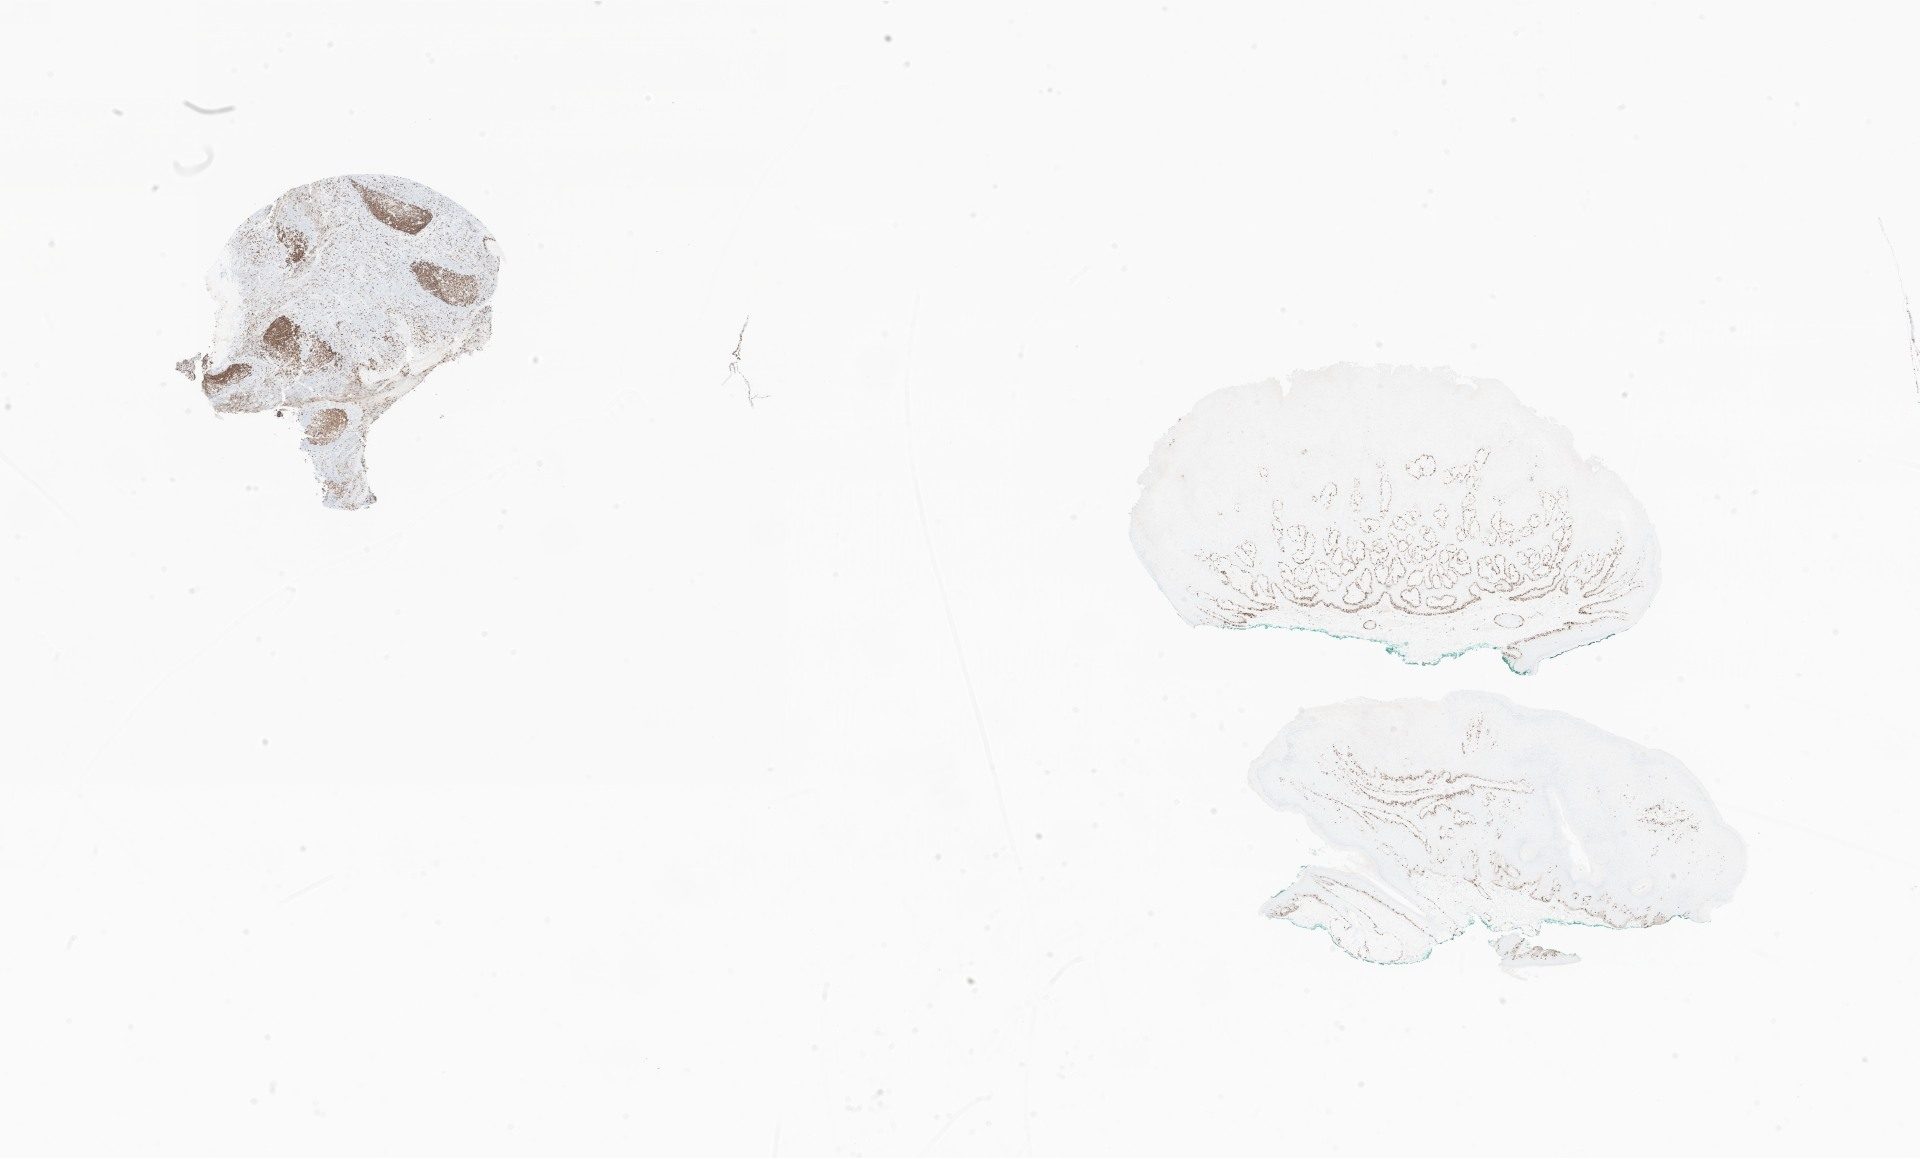

p16.svs

87370

x

40491

@

40X